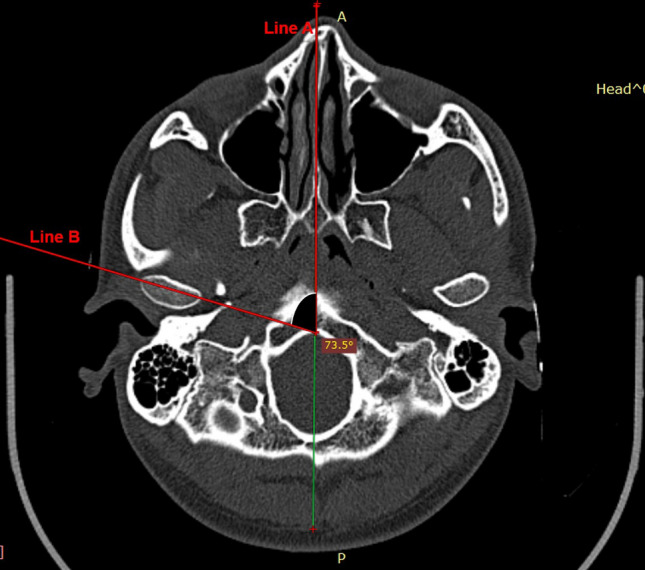

Preoperative (1 week prior to surgery) and postoperative (3 months post-surgery) computed tomography (CT) scans were obtained. All preoperative and postoperative CTs were taken with the patient biting in centric occlusion or maximum intercuspation. In axial scan images, the slice with the greatest mediolateral dimension of the condylar head was obtained for each side. A midsagittal line was drawn from the base of vomer to the midpoint of clivus of the sphenoid (line A). Line B was drawn along the axis of the condyle from the lateral pole to the medial pole. Axial rotation of the condyle was measured as a change in the angulation between lines A and B, indicating the medial or lateral rotation of the condyles (Fig. 3).

Fig. 3.

Condylar angle measurement on axial CT scan images